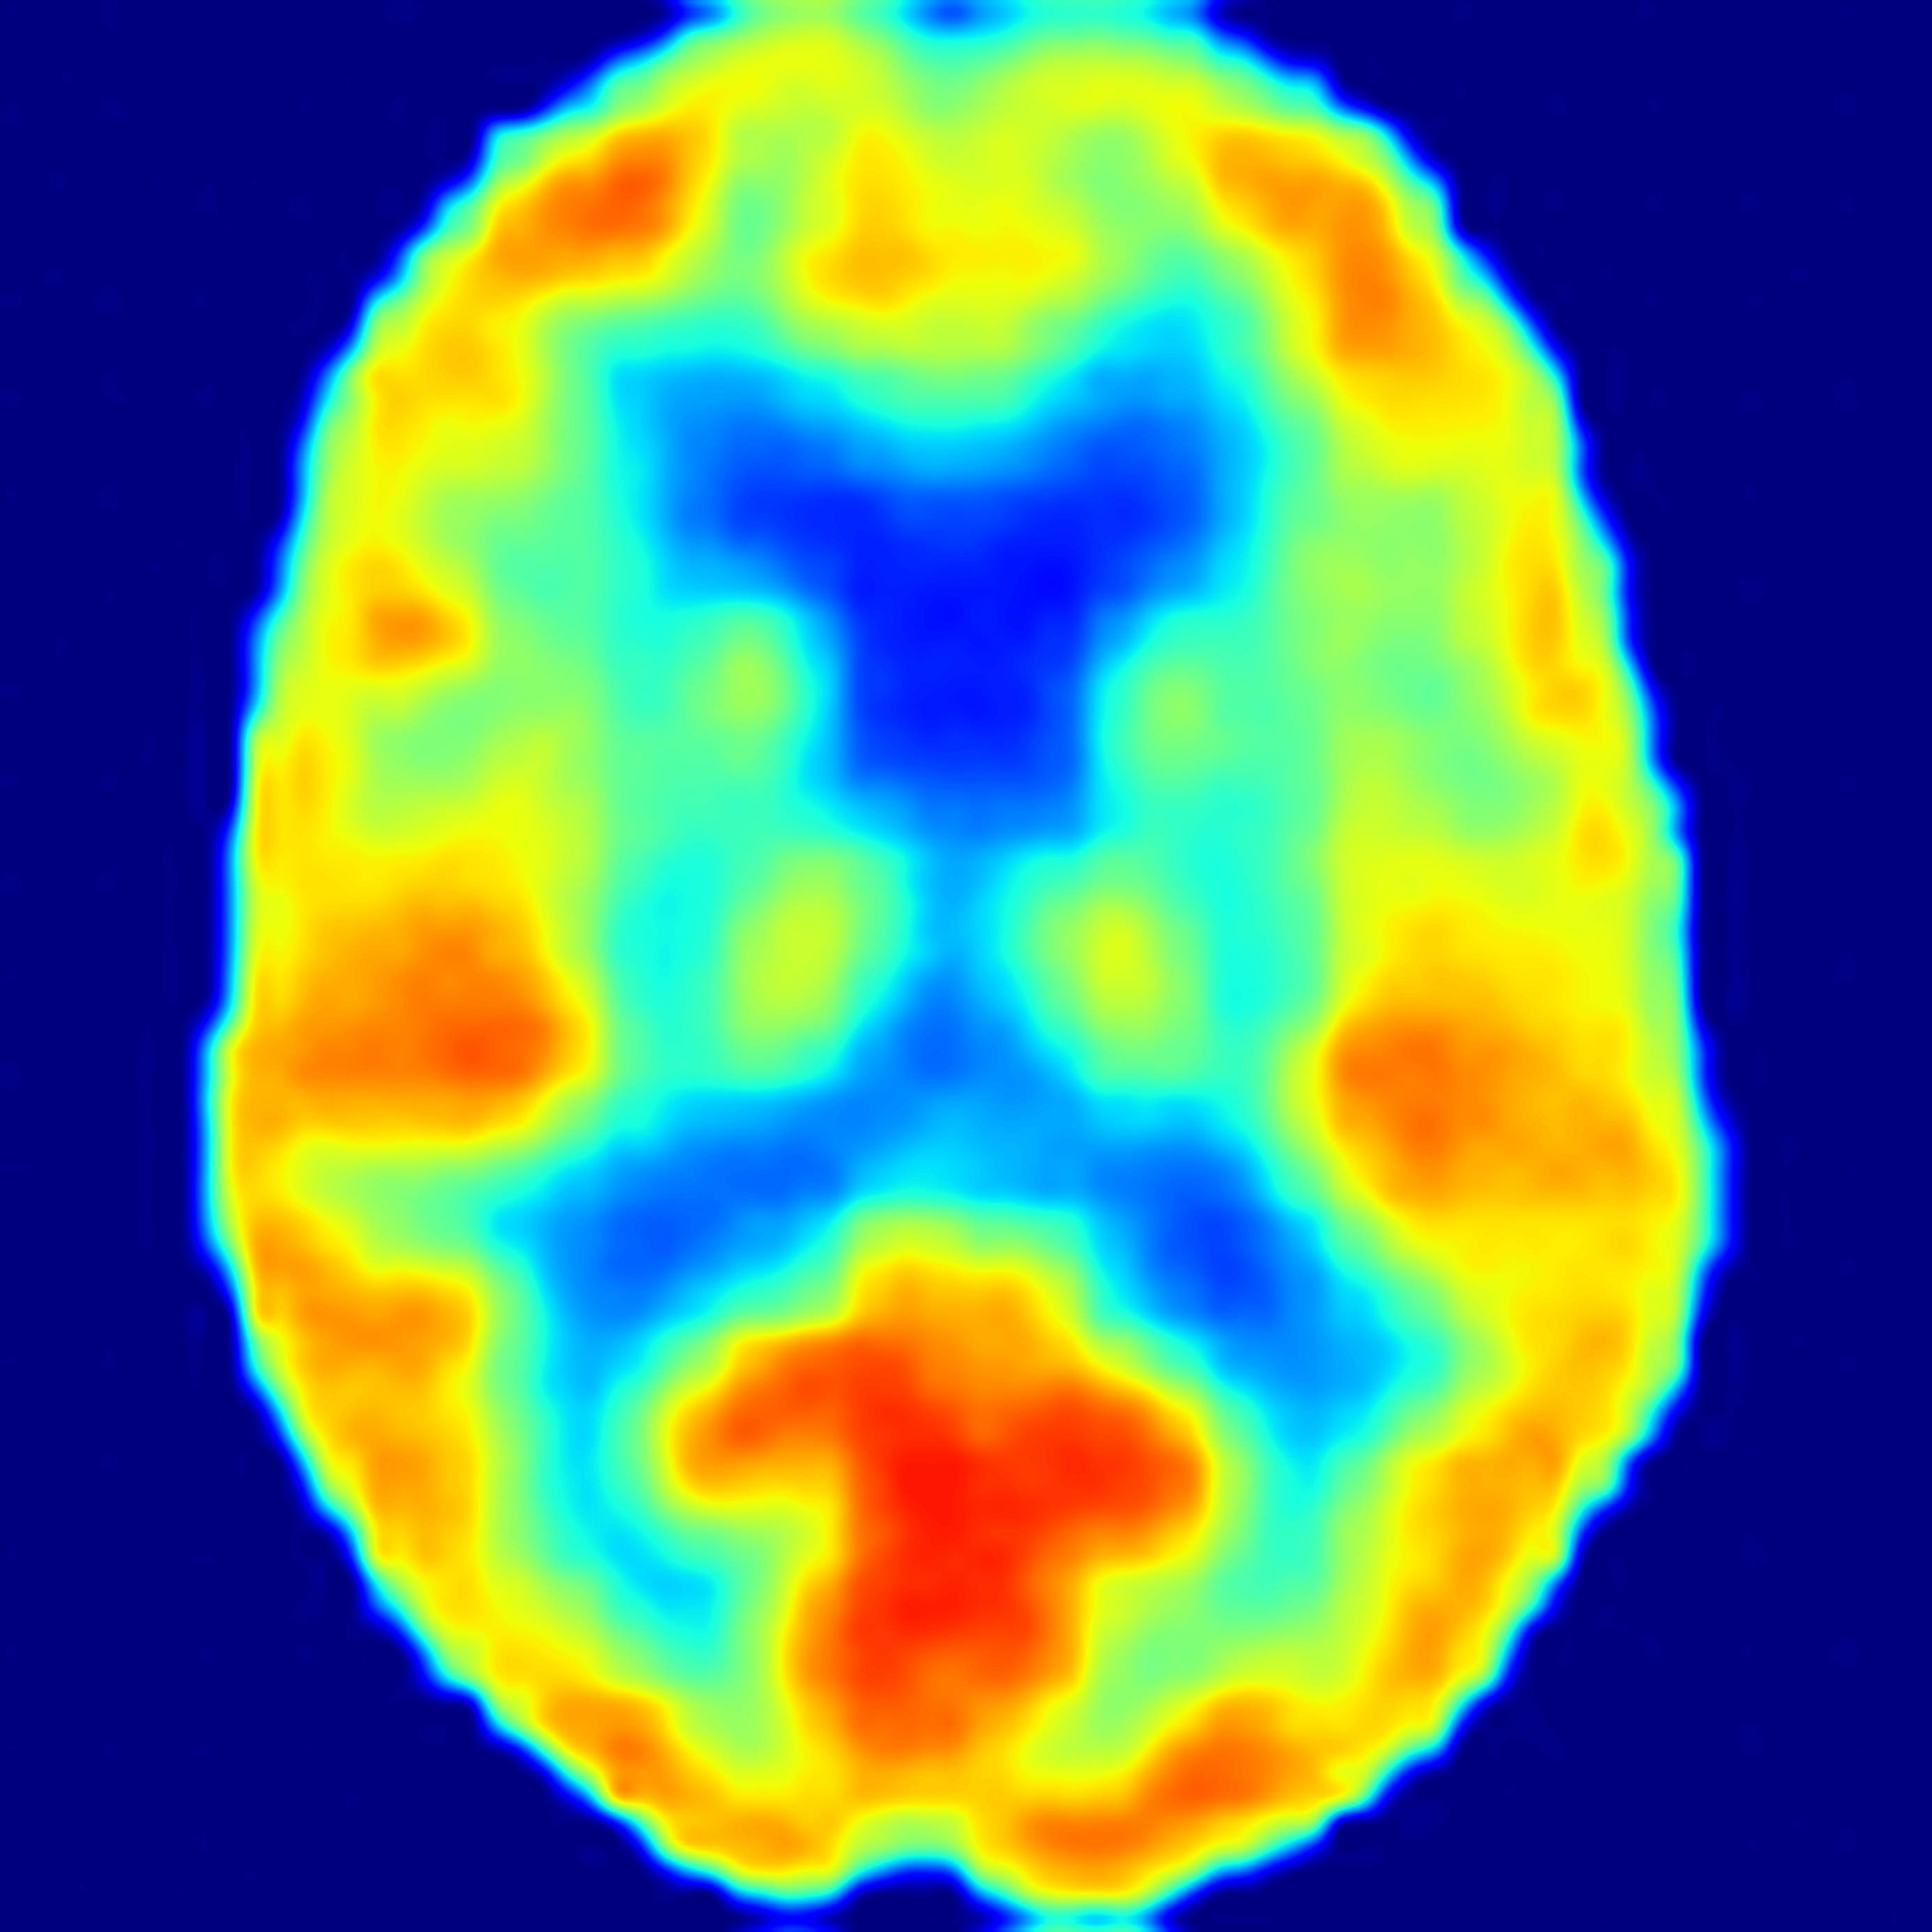

SiM2P simulates PET from MRI with high fidelity

(AD: Alzheimer's Disease, FTD: Frontotemporal Dementia, CN: Normal Control)

82 years old female with AD

66 years old female with AD

71 years old male with FTD

60 years old female with FTD

69 years old female as CN

70 years old male as CN

SiM2P employs a 3D diffusion bridge to simulate PET (SimPET) from structural MRI, conditioned on available auxiliary data. We validated the diagnostic utility of SimPET in a blinded clinical reader study, where SimPET showed significantly higher accuracy than MRI.

In a blinded clinical reader study, SimPET from SiM2P improved diagnostic accuracy by up to 12% over MRI across a range of tasks, with substantially increased interrater reliability.

SiM2P offers high pathological sensitivity even in scenarios where structural MRI lacks sufficient pathological atrophy, such as in early-stage or atypical presentations of AD.